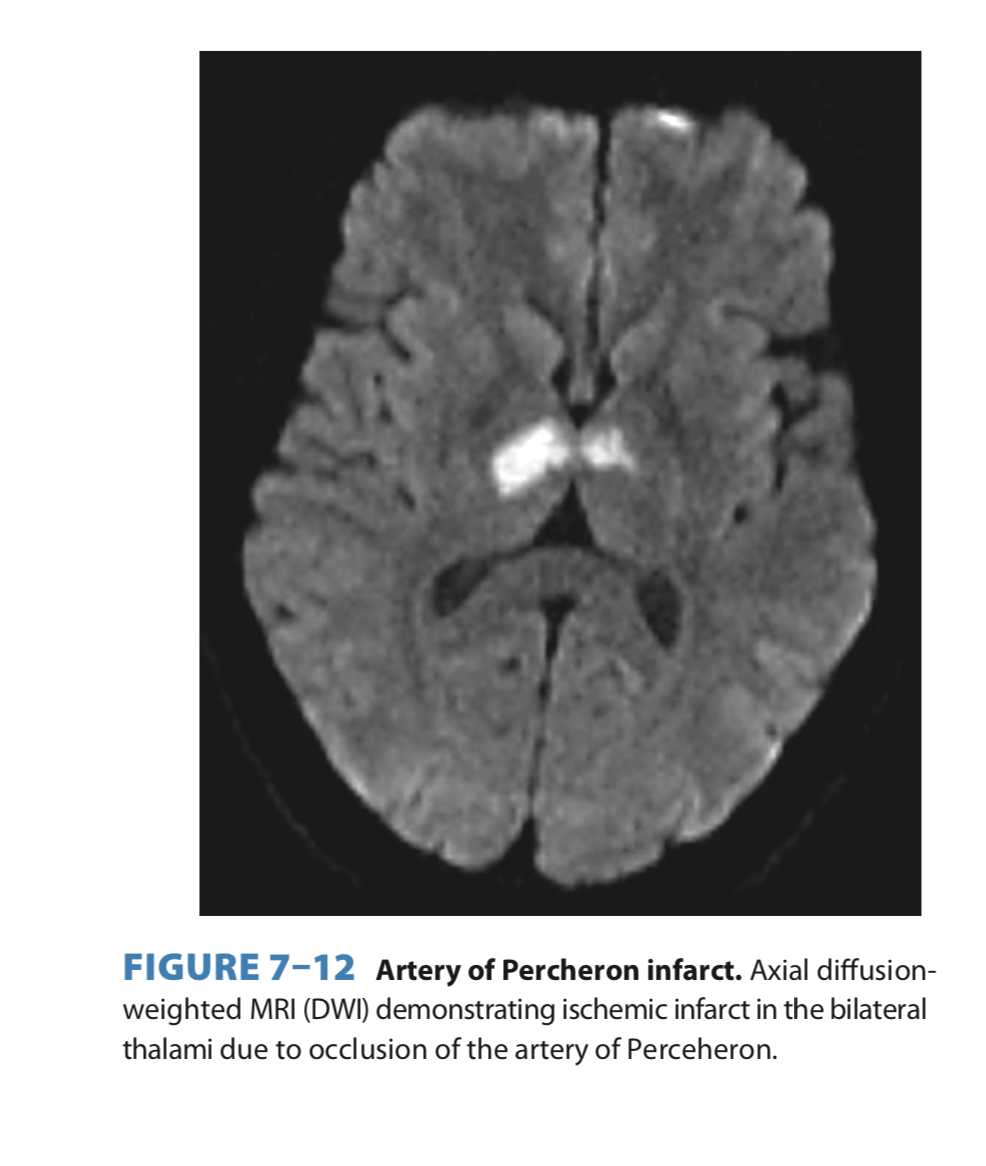

In general thalamus supplied by posterior circulation- PCA + branches... want more detail? check out amazing paper by @SchmahmannLab virtuoso neurologist Jeremy Schmahmann @MGHNeurology